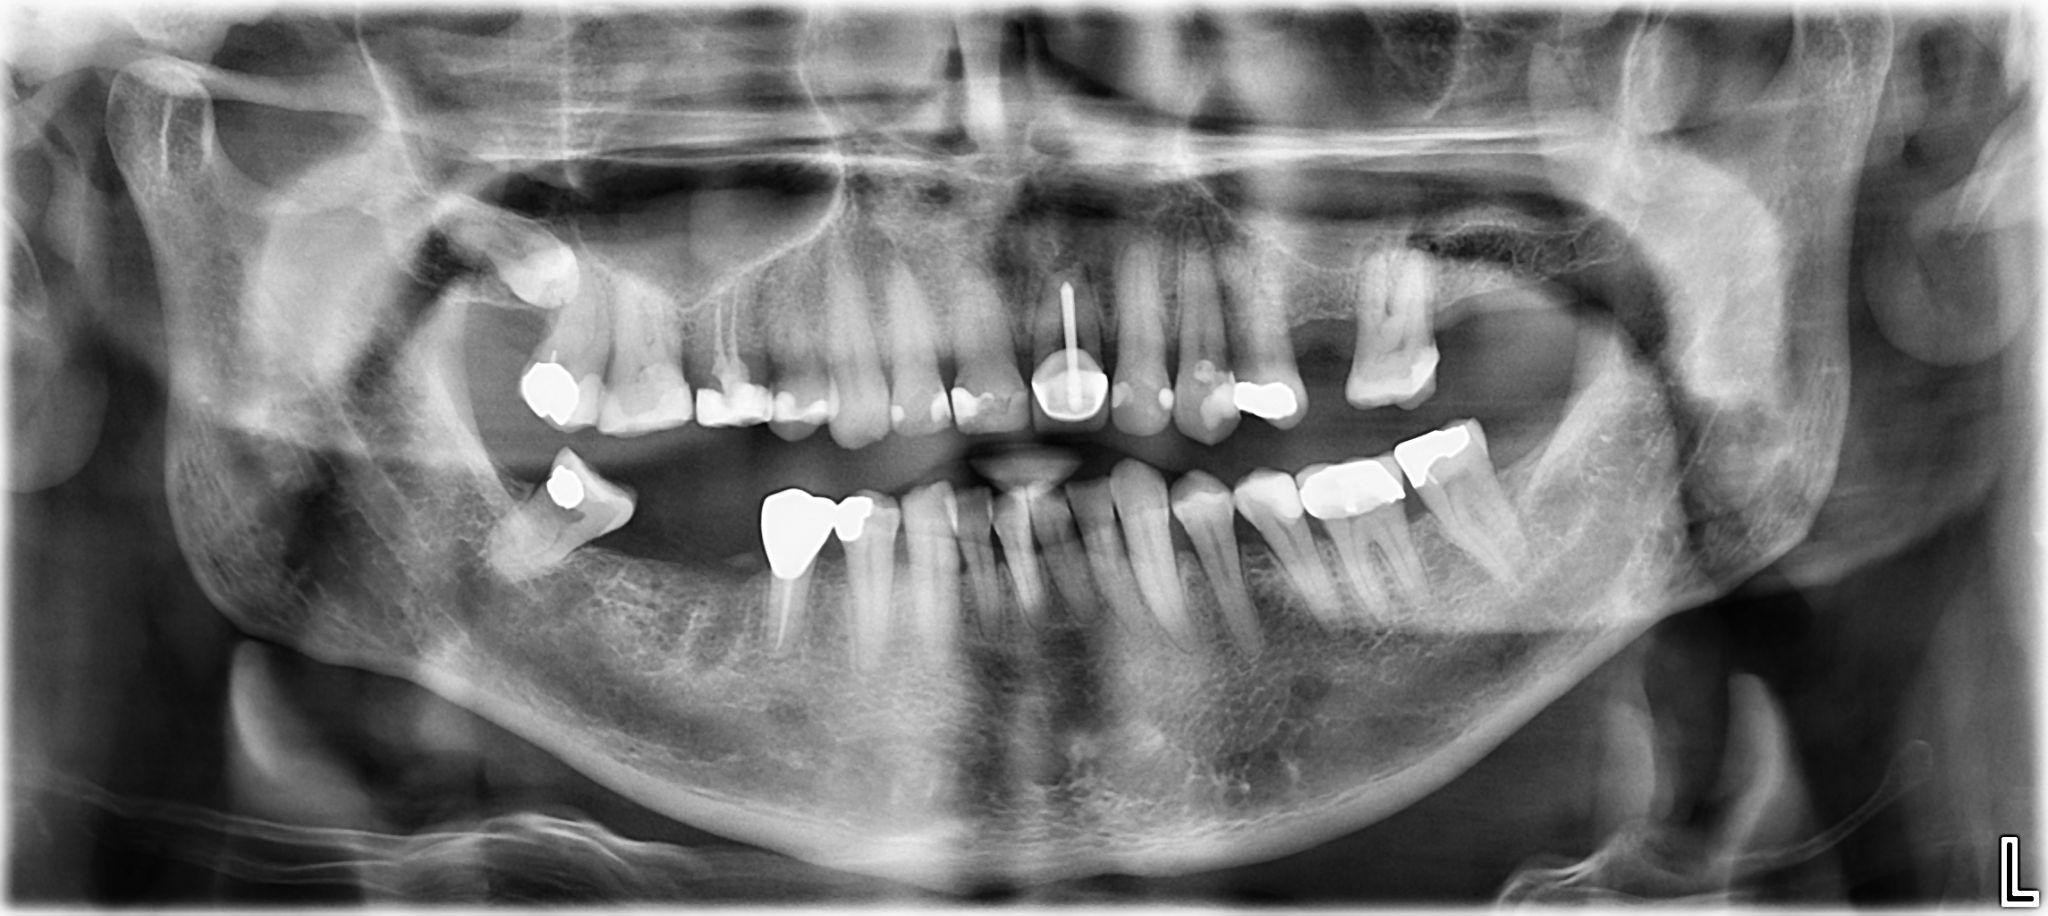

1. What option cannot be selected for the first quadrant of this panoramic X ray?

2 / 25

2. What option cannot be selected for the second quadrant of this panoramic X ray?

3 / 25

3. What option can be selected for the third quadrant of this panoramic X ray?

4 / 25

4. What option cannot be selected for the forth quadrant of this panoramic X ray?